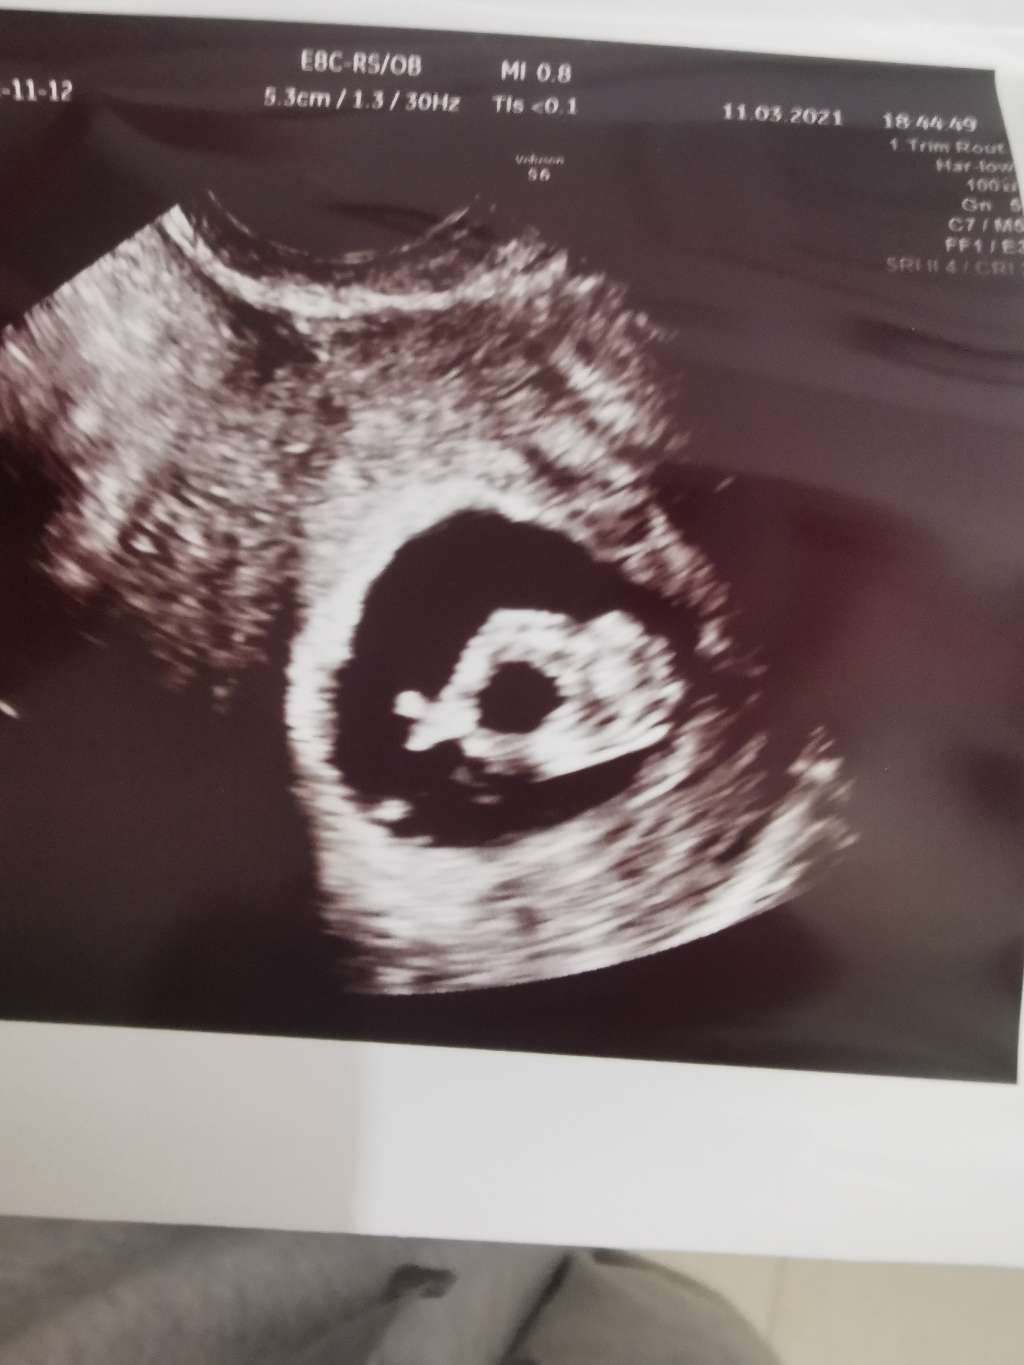

Faktycznie na tych zdjęciach to dużo trzeba się domyślać 😁 ale ja mam kilka fotek i na tym jednym np dobrze widać nóżki i stopki 😁

Załączniki

• 0aaa7b65-f284-4631-9c2d-4bc1aa6d4f65.jpg

0aaa7b65-f284-4631-9c2d-4bc1aa6d4f65.jpg

62,5 KB · Wyświetleń: 104